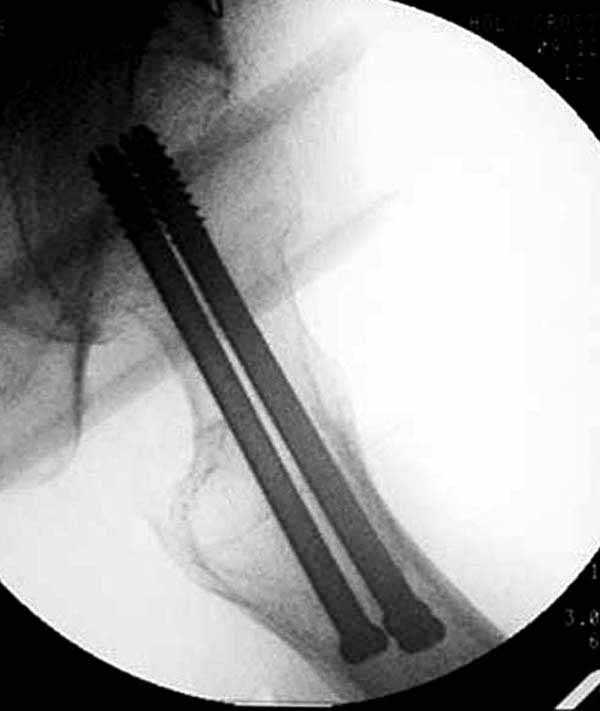

Пациентка Ш. 76 лет, 11 дней назад прооперирована по поводу вколоченного субкапитального перелома шейки левой бедренной кости, 3-мя канюлированными винтами. Вчера пациентка упала в палате. И вот результат- подимплантатный подвертельный перелом левой бедренной кости. Уважаемые коллеги, пожалуйста посоветуйте какой метод дальнейшего лечения предпринять дальше.Соматически пациента повышенного питания, страдает варикозной болезнью нижних конечностей.Из предложенных вариантов коллег - целллокастовая укороченная кокситная повязка, скелетное вытяжение сроком на 40-45 суток - отпали сразу, так как необходимо активизация пациентки.На данный момент рассматриваем следующие варианта реостеосинтеза:(наличие технических возможностей) 1. Длинная Gamma 3 Stryker (с предварительной интраоперационной фиксацией головки спицами).2. Трохантерный штифт DePuy с 2-мя метафизарными винтами в проксимальном отделе, (также с интраоперационной фиксацией головки спицами. Очень настораживает стабильность фиксации с проксимальном отделе с связи с выборкой костной ткани ранее находящимися там канюлированными винтами. Сейчас пациентка находится на скелетном вытяжении, с дисциплинирующим грузом. Операция планируется после праздников. Заранее извиняемся за качество и неполное соответствие проекций на R-ммах (R-служба отдельная песня). При интраоперационном ЭОП-контроле винты в аксиальной проекции разнесены по шейке.

1. винты расположены не в лучшем положении:

два в нижней части шейки. Более стабильная структура как раз обратная: два шурупа в проксимальной части шейки , и не дальше центральной части головки, иначе есть риск пенетрации. дистальный винт мог бы быть выше уровня малого вертела. Его дистальное расположение описано с увеличенным риском послеоперационного перелома.

Как отметили коллеги, необходимо обратить внимание на последовательность введения каннюлированных шурупов. Рекомендуется введение в форме “V”, т.е основанием вниз, потому что в другой последовательности за счет увеличения стресса латерального кортекса имеется риск перелома. За редким исключением удается установить Guide wire с первой попытки и многоразовые пробы спицей увеличивают стресс. Небольшая травма может привести к перелому.

Работа Burstein AH and Wright TM: Fundamentals of Orthopaedic Biomechanics. Williams & Wilkins, Baltimore, pp. 160-169, 1994 доказывает, что шурупы, введенные на уровне малого вертела или ниже, приводят к осложнению. Введенные шурупы под 135 и больше градусов в 20% осложнились подвертельными переломами бедра.